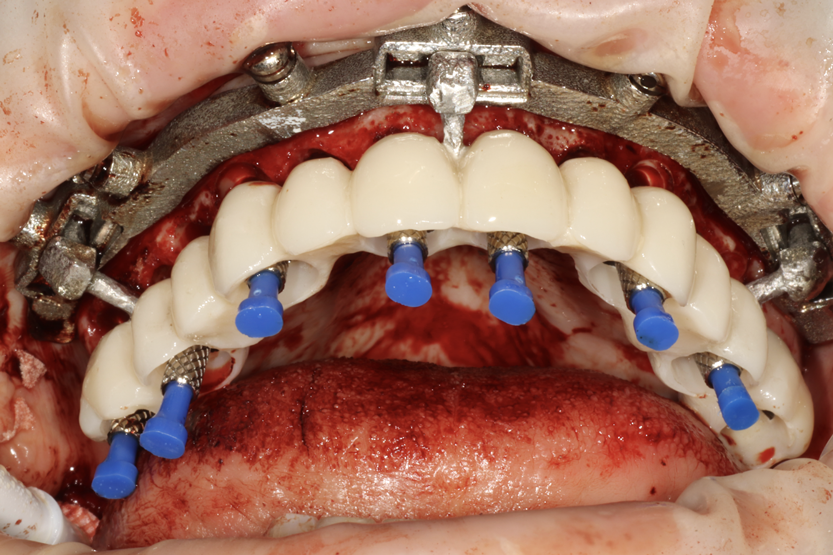

Importantly, patients for whom implant placement is being planned may have previously undergone root canal treatment utilizing radio-opaque materials or have amalgam, metal, or metallo-ceramic restorations, or they may even have previous implants. When x-ray beams pass through these radio-opaque objects, the resulting CBCT images often have metallic scatter (Figure 1, left panel). The artifacts or noise created by the metallic or metallic-like substances degrade the image quality and induce cupping or streaks. This can be particularly troublesome when the clinician is attempting to diagnose dental conditions or to fabricate surgical guides.

Previous CBCT softwares utilized the FDK (Feldkamp, Davis, and Kress) algorithm or SART (simultaneous algebraic reconstruction technique ).12 For many years, the quality of CBCT scans required additional steps to reduce the amount of scatter; often a tray or fiducial device would be required in the CBCT patient capture and again in a standalone capture. However, advancements in CBCT such as metal artifact reduction (MAR)13 (Figure 1, right panel) and beam hardening removal have helped address these challenges in obtaining high-quality scans. Projection-based MAR algorithms act in projection space and replace corrupted projections caused by metal with interpolation from neighboring uncorrupted projections. By reducing scatter and artifacts, these enhanced tools of MAR allow for a simplified matching between 3D radiography and the digital impressions, allowing users to expedite planning and treatment as a whole. Once the files have been merged, proper treatment planning can begin.

Fig 1. CBCT using the Feldkamp, Davis, and Kress (FDK) algorithm (left panel) and metal artifact reduction (MAR) algorithm (right panel). Note

the visible scatter and hardening associated with FDK is absent when MAR is used, and the bone quality is sharper and more defined with the

MAR image.